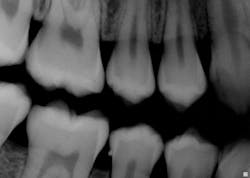

The patient today is a 15-year-old female who has a scheduled appointment for a dental prophylaxis with radiographs. While viewing the radiographs, the hygienist notices the presence of an enamel pearl on No. 29 distal (see Figure 1). The patient did not bring any previous radiographs with her for the appointment and, fortunately, radiographs were taken before the scaling procedure was performed. If scaling had been completed prior to recognizing that the enamel pearl was present, the appointment may have taken a totally different course. The enamel pearl would have been discovered during scaling; the potential for a broken instrument tip lodging in the tissue would have been a possibility.

Figure 1: Courtesy of Dr. Kathryn Savitsky, Charlotte, N.C.